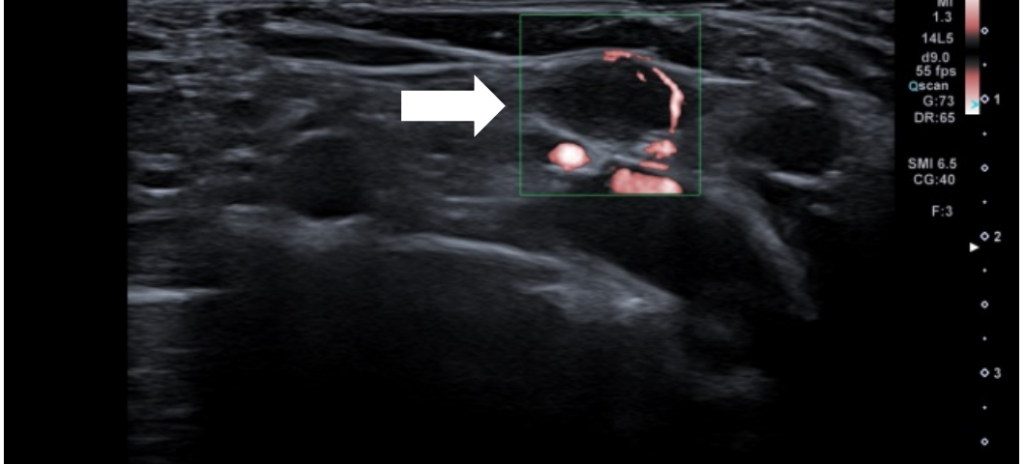

Juni 2020 – Bruk av Superb Microvascular Imaging (SMI) ved evaluering av lymfeknutevaskulatur i ung pasient med brystkreft

Ei 29 år gammal kvinne kjem til brystdiagnostisk poliklinikk med ein øm klump i høgre bryst og palpalble aksillære lymfeknuter. Ho var frå før frisk utan brystkreft i familien. Ultralyd […]